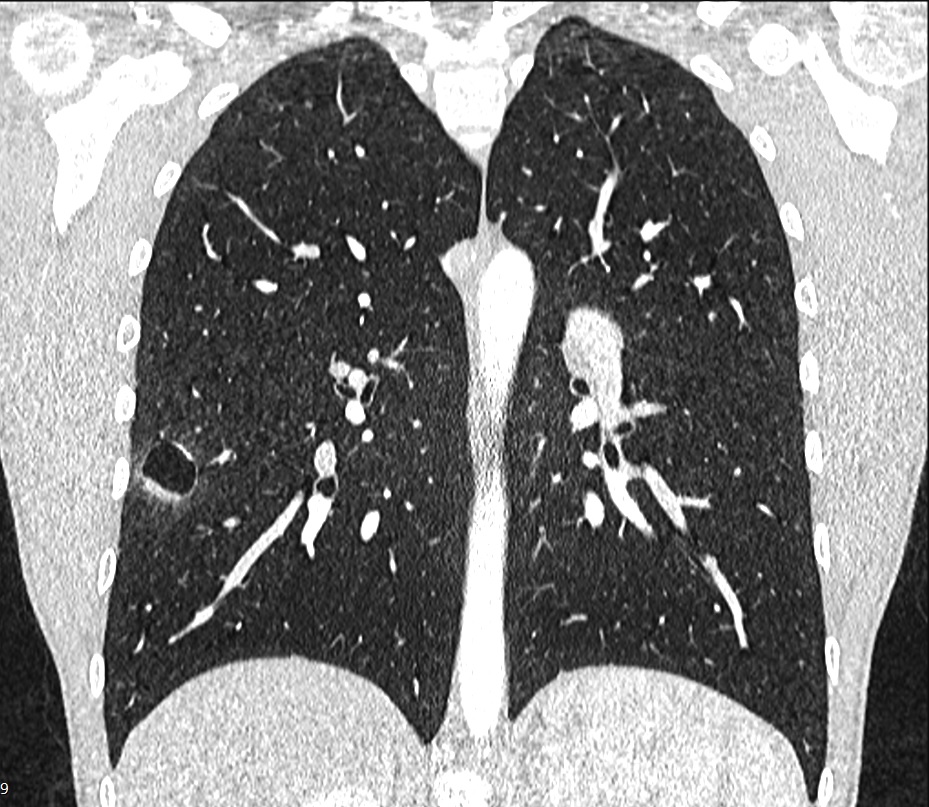

Figure 2. Cavitary lesion in the right basomedial segment.

The authors report on the case of a 15-year-old male patient who presented with a two-year history of recurrent hemoptysis (about 60 ml), occurring once every three to four weeks. The hemoptysis was not related to physical activity or other respiratory symptoms and was self-limiting. The patient underwent a diagnostic fiber optic bronchoscopy that was inconclusive. A chest CT scan showed a cavitary lesion in the right basomedial segment of the right lower lobe of the lung. The patient's case was discussed in a multidisciplinary board meeting, and it was agreed that the right lower lobe lung lesion was the most probable cause of the patient's condition. The team planned a thoracoscopic uniportal video-assisted segmental resection of the right basomedial segment of the right lower lobe. The operative course was uneventful. The chest tube was removed three hours after the surgery, and the patient was discharged home on postoperative day one.

The characteristic radiological presentation of IMTs is usually a peripheral, solitarily, sharply circumscribed lobulated mass. These lesions can be located in the parenchyma (85.7% of cases), endobronchial (10.7% of cases), and endotracheal in (3.6% of cases) (3). To the best of the authors’ knowledge, there are a very limited number of reported IMT cases with cavitary presentation. The authors will continue to monitor the patient annually for recurrence of the IMT or hemoptysis symptoms.